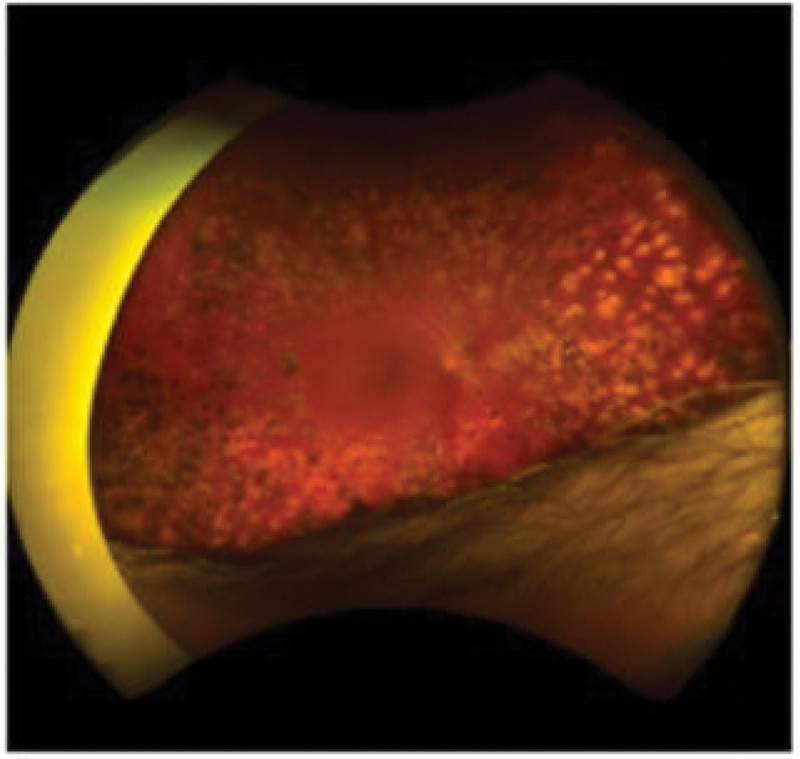

Background: Retina fundus images conducted in Greenland are telemedically assessed for diabetic retinopathy by ophthalmological nurses in Denmark. Applying an AI grading solution, in a Greenlandic setting, could potentially improve the efficiency and cost-effectiveness of DR screening.Method: We developed an AI model using retina fundus photos, performed on persons registered with diabetes in Greenland and Denmark, using Optos® ultra wide-field scanning laser ophthalmoscope, graded according to ICDR.Using the ResNet50 network we compared the model's ability to distinguish between different images of ICDR severity levels in a confusion matrix.Results: Comparing images with ICDR level 0 to images of ICDR level 4 resulted in an accuracy of 0.9655, AUC of 0.9905, sensitivity and specificity of 96.6%.Comparing ICDR levels 0,1,2 with ICDR levels 3,4, we achieved a performance with an accuracy of 0.8077, an AUC of 0.8728, a sensitivity of 84.6% and a specificity of 78.8%. For the other comparisons, we achieved a modest performance.Conclusion: We developed an AI model using Greenlandic data, to automatically detect DR on Optos retina fundus images. The sensitivity and specificity were too low for our model to be applied directly in a clinical setting, thus optimising the model should be prioritised.

Abstract Image